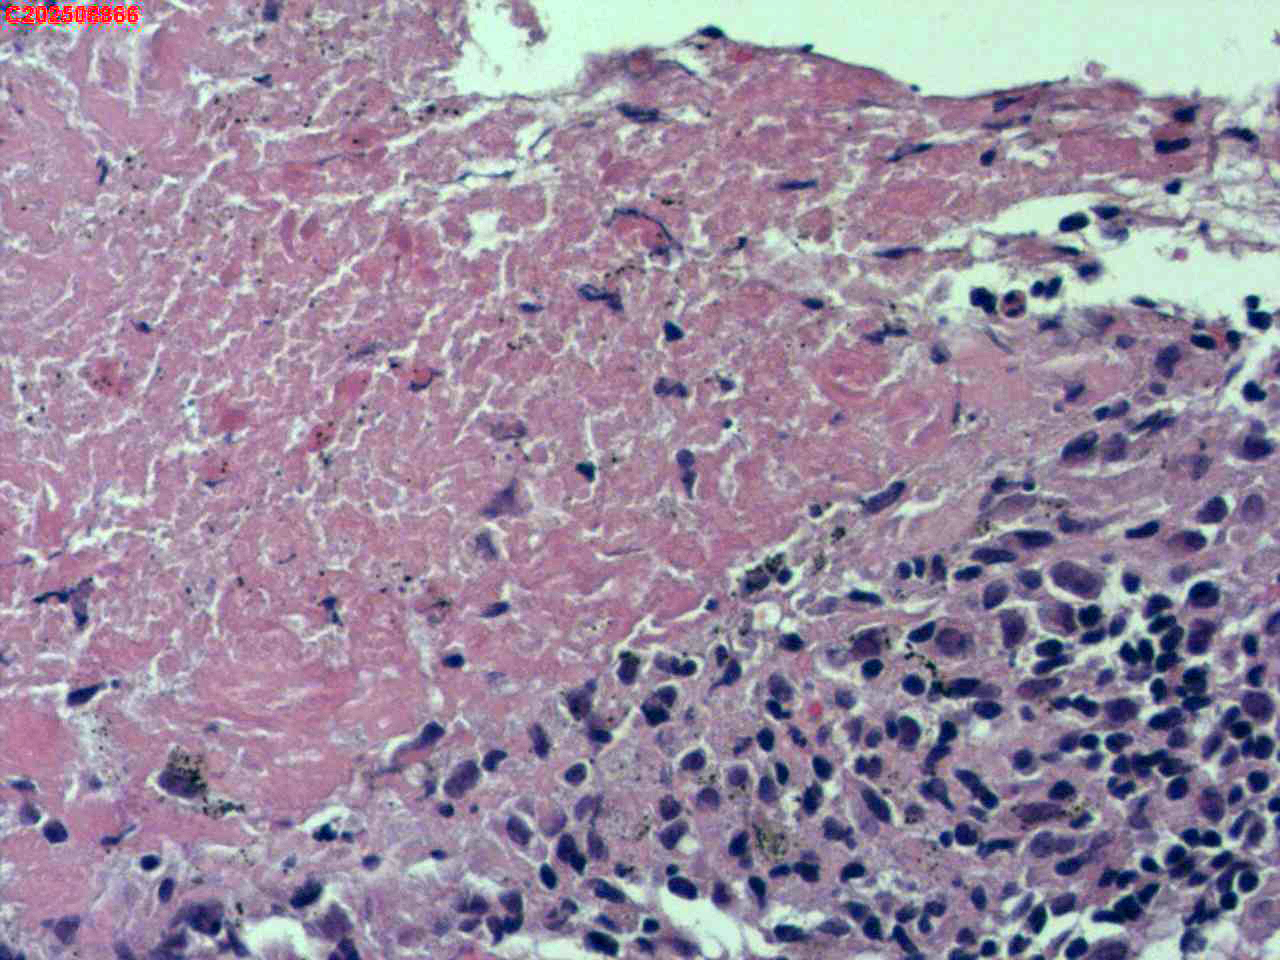

纤支镜咬检

肺TB?Ca?

胸部CT(平扫):考虑双肺感染性病变,结核?支气管炎?请结合临床及其它检查。

标本名称

右肺上叶后段开口咬检组织

大体所见

右肺上叶后段开口处粘膜不规则增生。

肉芽肿性炎的可能性大些!

有坏死,深染变形的细胞需要排一排神经内分泌肿瘤。